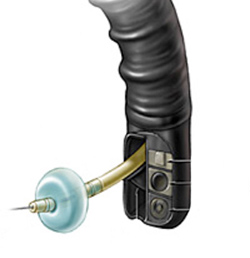

Durante o procedimento o paciente é sedado como em toda a endoscopia digestiva. Então na ponta do aparelho é acoplado o dispositivo de ligadura elástica, ficando a manopla de disparo dos elásticos na outra extremidade do endoscópio, no local onde o endoscopista realiza as manobras com o aparelho.

Após a introdução do aparelho o endoscopista identifica as veias dilatadas (varizes) e aspira o ponto a ser ligado para dentro do dispositivo. Após isto, gira o dispositivo de ligadura soltando o anel de borracha, que estrangula a porção da variz que foi aspirada.